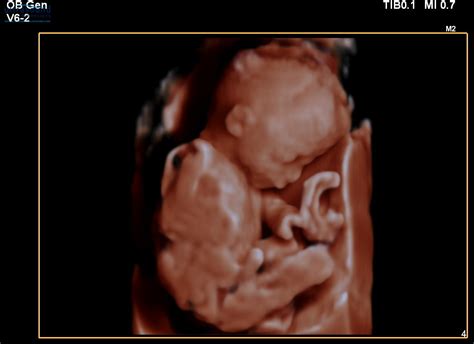

Hey guys, let’s talk about something super important and frankly, a bit nerve-wracking: the 20-week scan . This scan, often called the anomaly scan, is a big deal. It’s usually the most detailed ultrasound you’ll have during your pregnancy, and it’s designed to check on your little one’s development, looking at everything from their tiny fingers and toes to their major organs. It’s a time when many parents-to-be get really excited to see their baby and find out if they’re having a boy or a girl! But what happens when the scan reveals something unexpected, or, dare we say, bad news? This is a topic that pops up on forums like Reddit and Mumsnet quite a bit, and for good reason. Facing the possibility of complications or an unexpected diagnosis at this stage can be incredibly overwhelming. It’s natural to feel a whirlwind of emotions – shock, fear, sadness, anger, and confusion. You might find yourself replaying the scan in your head, wondering if anything could have been done differently, or if you missed any signs. The medical team performing the scan is highly trained to look for specific markers that might indicate a potential issue. They’ll be examining the baby’s brain, heart, lungs, kidneys, stomach, spine, and limbs, as well as the placenta and umbilical cord. If they spot something that doesn’t look quite right, they won’t just ignore it. They’ll usually have a discussion with you right there and then, or schedule a follow-up appointment with a specialist. It’s important to remember that sometimes what looks concerning on a scan might turn out to be nothing serious, or it might be something manageable. However, being prepared for the possibility of difficult news is part of the journey for some expectant parents. This article aims to shed some light on what to expect if you receive bad news at your 20-week scan, how to navigate the emotional rollercoaster, and where to find support. We’ll delve into the common reasons for concern, the next steps involved, and how to cope with the uncertainty and challenges that may arise. It’s a heavy topic, but having information can be a powerful tool in managing anxiety and making informed decisions.

Alright, let’s dive deeper into the 20-week anomaly scan , because understanding what the sonographer is actually looking for can help demystify the process and perhaps ease some of the pre-scan jitters. This scan is pretty comprehensive, guys. The primary goal is to check for major structural abnormalities in the baby’s development. Think of it as a detailed road map of your baby’s anatomy. They’ll meticulously examine the baby’s head, checking the brain for development and structure. They’ll look at the face, including the lips and palate, to check for cleft lip or palate. The heart is a big focus, with them assessing the four chambers and the major blood vessels to ensure they’re forming correctly. They’ll also examine the baby’s abdomen, looking at the stomach, intestines, and kidneys. The spine is checked for any gaps or abnormalities, and all four limbs – arms, legs, hands, and feet – are carefully counted and assessed. The placenta is checked for its position and to make sure it’s providing adequate blood flow to the baby, and the umbilical cord is examined for the correct number of blood vessels. It’s crucial to understand that this scan is a screening tool, not a diagnostic test for everything. While it’s incredibly thorough, it’s not foolproof. Some minor issues might not be visible on the scan, and some conditions only become apparent later in pregnancy or after birth. When the sonographer is performing the scan, they are looking for deviations from what is considered typical development. This could range from something relatively minor, like a slight difference in limb length that might resolve on its own, to more significant concerns like congenital heart defects, spina bifida, or certain genetic syndromes. They’re comparing the baby’s measurements and appearance against established growth charts and developmental milestones. If they notice something that falls outside the normal range, they are trained to flag it. This doesn’t automatically mean there’s a serious problem, but it does mean further investigation is often needed. For example, a bright spot in the baby’s heart might be a common finding that doesn’t affect the baby’s health, but it will be noted. Similarly, a slight delay in organ development might prompt a follow-up scan or referral to a specialist. The key takeaway here is that the medical professionals are doing their best to provide the healthiest possible outcome for you and your baby. They are trained observers, looking for subtle and not-so-subtle signs of potential issues. The goal isn’t to scare anyone, but to be proactive and catch anything that might require medical attention or planning before birth. It’s a vital part of prenatal care that provides invaluable information, even when that information is challenging to receive.